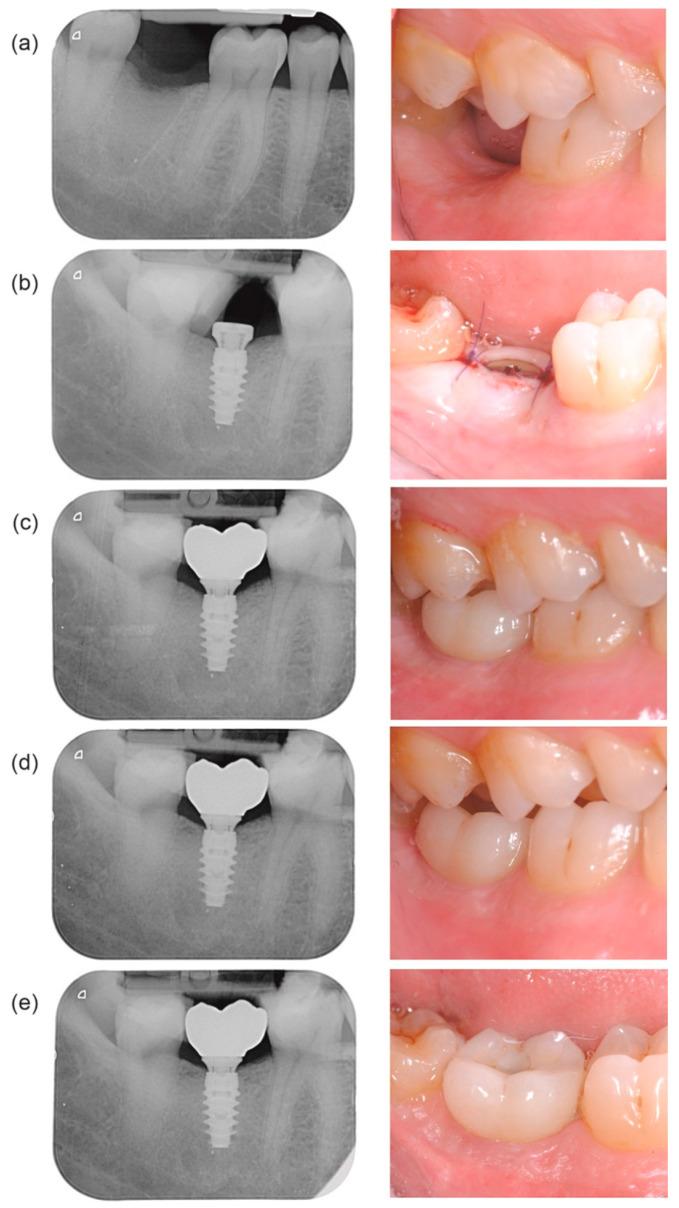

Development of a stable and healthy soft-tissue barrier around dental implants is key to long-term success of implant-supported prostheses. The novel two-piece abutment concept shifts the prosthetic interface to the soft-tissue level to protect bone interface/connective tissue during the healing phase and restorative procedures. This prospective study included 72 patients treated with 106 implants to support a single-tooth or a three-unit bridge restored with two-piece abutments. The evaluation included marginal bone level change (MBLC), implant and prosthetic survival, soft-tissue health including keratinized mucosa height and mucosal margin position, patient quality of life (QoL) and satisfaction, and clinician satisfaction and ease-of-use rating of the concept. Mean MBLC from implant placement to 1 year was -0.36 ± 1.26 mm ( = 89), the 1-year implant and prosthetic survival rates were 97.1 and 96.7%, respectively, while keratinized mucosa height increased from 2.9 ± 1.2 mm at prosthetic delivery to 3.2 ± 1.3 mm, and mucosal margin migrated coronally by 0.49 ± 0.61 mm by 1 year. Patient satisfaction and QoL were high. Clinicians were satisfied with the esthetic and functional results and rated the concept as easy to use. In conclusion, the novel two-piece abutment concept promotes good peri-implant tissue health, while providing an easy-to-use workflow and high treatment satisfaction to both patients and clinicians.

在牙种植体周围形成稳定且健康的软组织屏障是种植体支持修复体长期成功的关键。新颖的两件式基台概念将修复界面转移至软组织层面,以在愈合期和修复过程中保护骨界面/结缔组织。这项前瞻性研究纳入了72例患者,共植入106颗种植体,用于支持单颗牙或用两件式基台修复的三单位桥体。评估内容包括边缘骨水平变化(MBLC)、种植体和修复体存留率、软组织健康状况(包括角化黏膜高度和黏膜边缘位置)、患者生活质量(QoL)和满意度,以及临床医生对该概念的满意度和易用性评分。从种植体植入至1年时的平均MBLC为-0.36±1.26 mm(n = 89),1年时种植体和修复体的存留率分别为97.1%和96.7%,而角化黏膜高度从修复体交付时的2.9±1.2 mm增加至3.2±1.3 mm,到1年时黏膜边缘向冠方迁移了0.49±0.61 mm。患者满意度和生活质量较高。临床医生对美学和功能效果感到满意,并认为该概念易于使用。总之,新颖的两件式基台概念可促进良好的种植体周围组织健康,同时为患者和临床医生提供易于使用的工作流程和较高的治疗满意度。